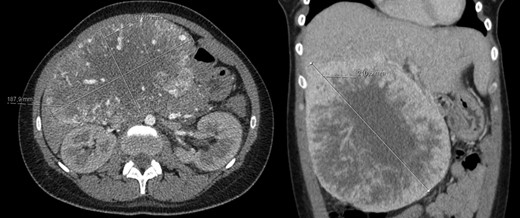

A 78-year-old woman with past medical history of hypertensive cardiopathy and bearer of a pacemaker, was referred to our Hepatobiliary Unit with diagnose of a liver mass discovered on CT scan, which was performed after complaints of nausea and postprandial infarction. CT scan (Fig. 3) showed a voluminous heterogeneous, lobed mass, displaying heterogeneous uptake contrast, relatively vascularized, localized in segment 1, with exophytic growth to the left lobe, with 18.5 × 13.8 × 15.6 cm; the tumor caused deviation of the stomach to the left.

AP-CT – voluminous heterogeneous mass in segment 1 with 18.5 cm in diameter.